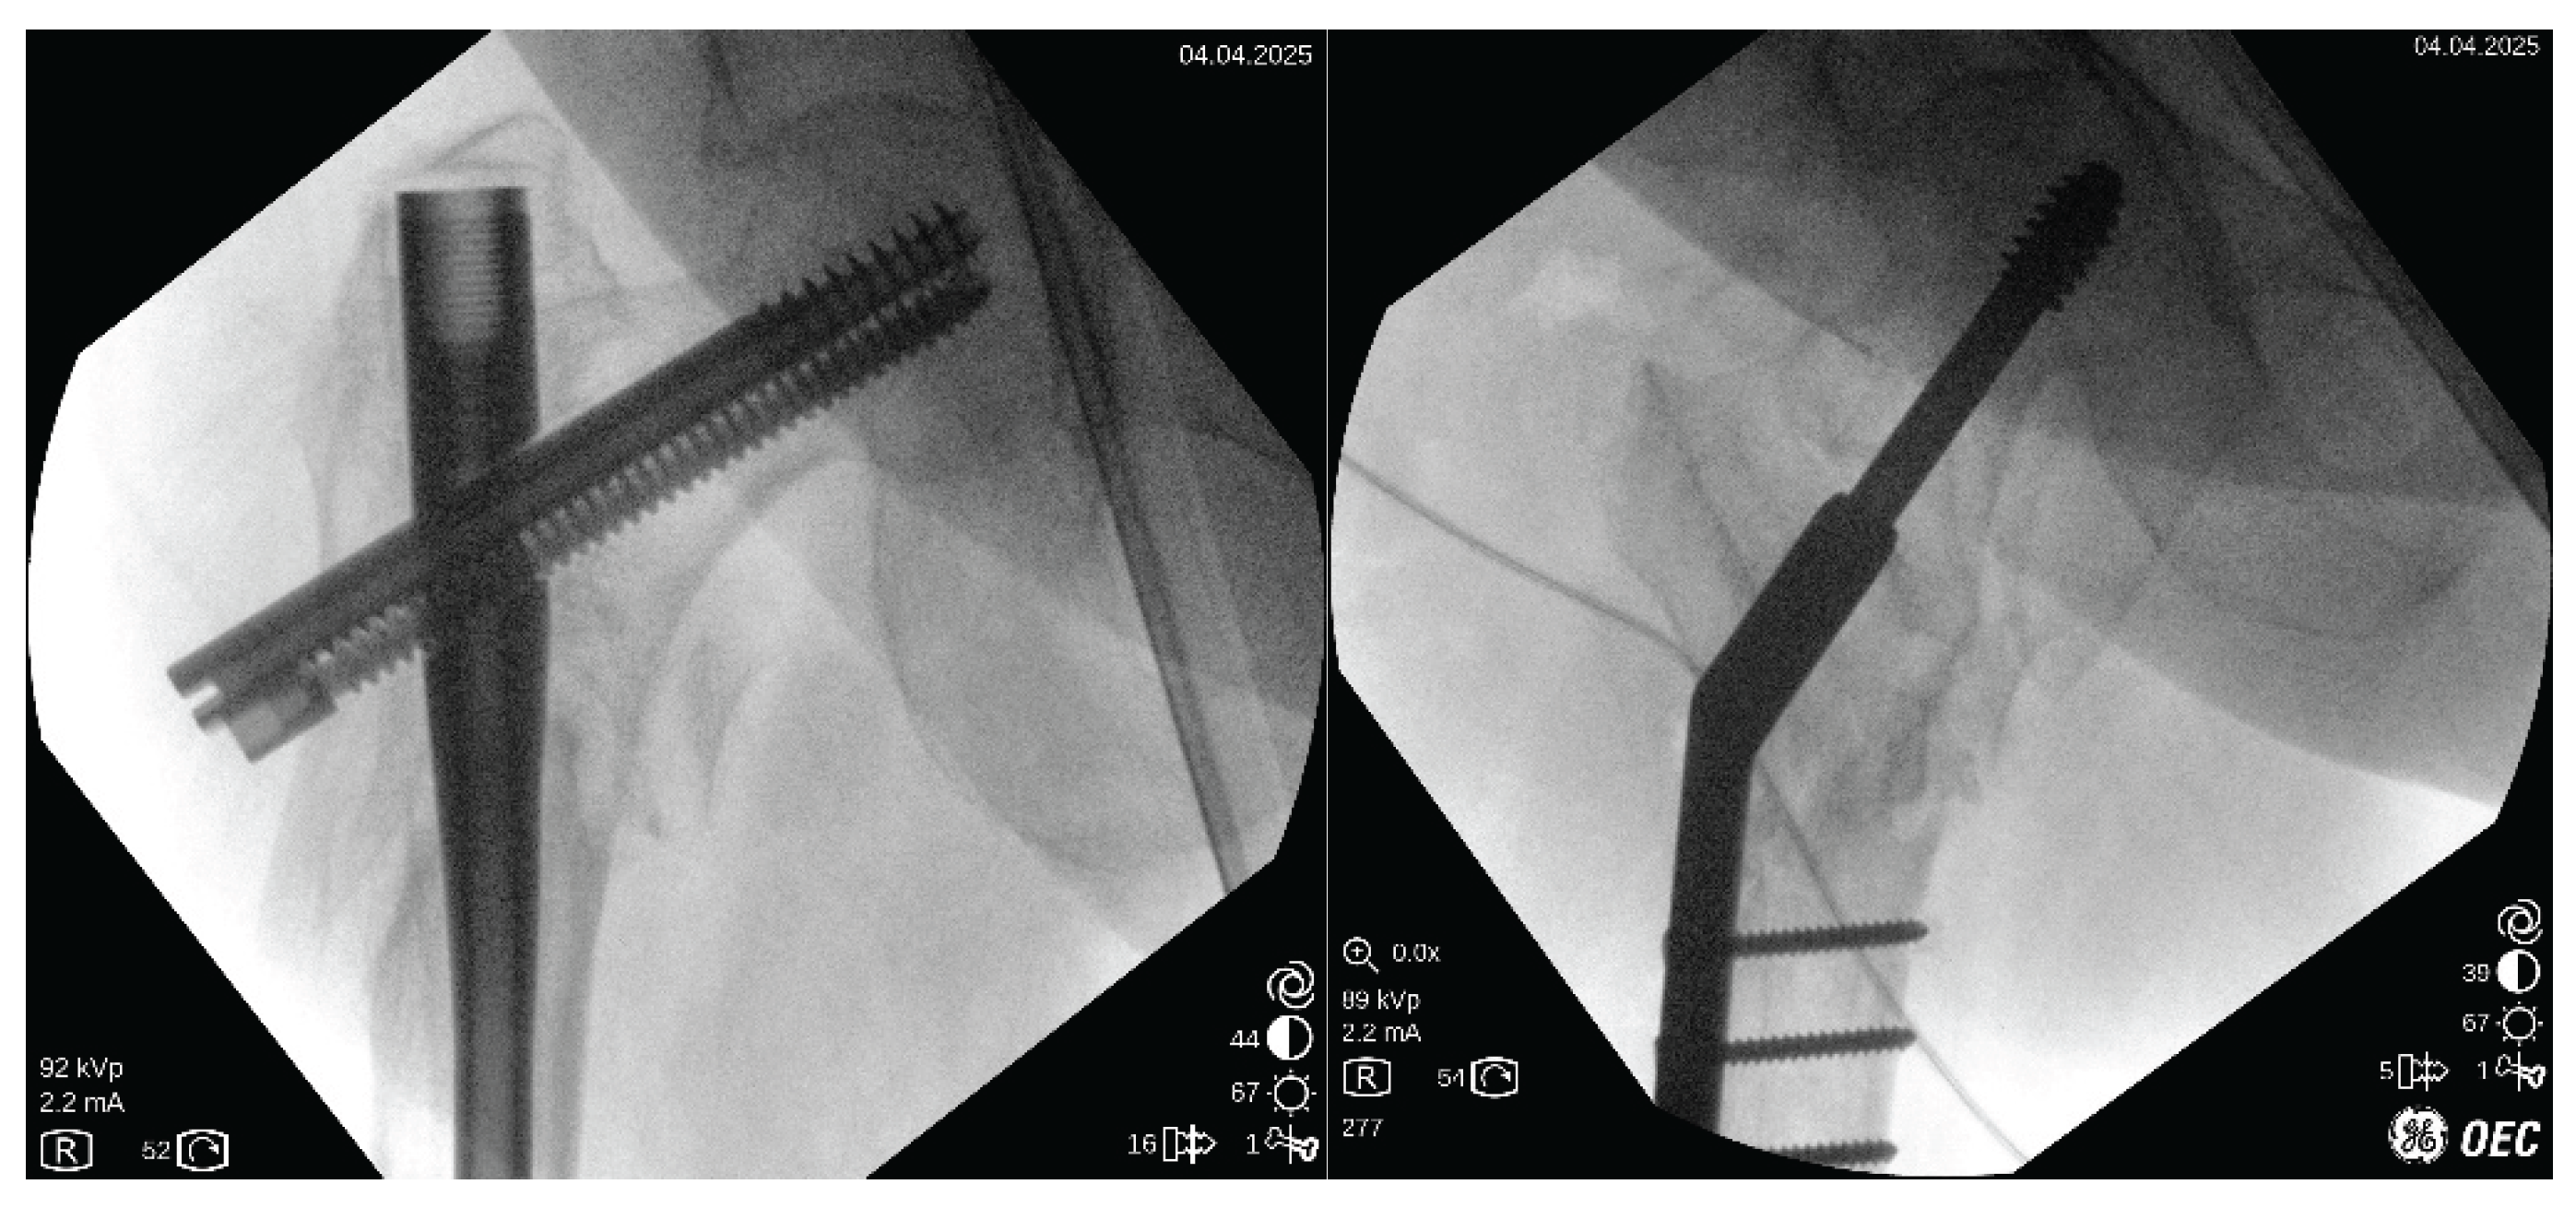

Good purchasing is verified by moving the construct under fluoroscopic vision (Figure 7).

Figure 7. Left: nonunion just before operation. Right: Final fixation as seen in fluoroscopy with 4 holes, 150º DHS. Observe the valgus correction, and increase in length.